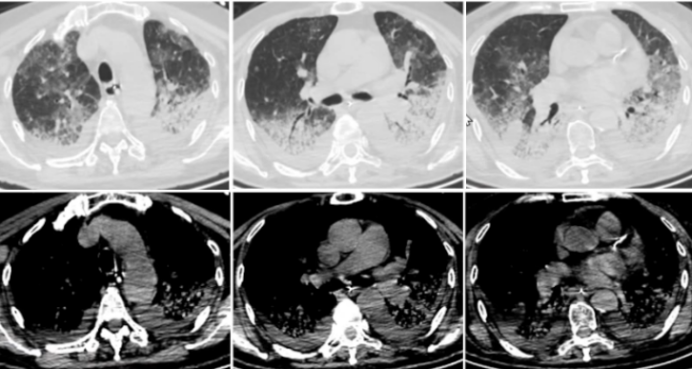

患者半年前无明显诱因出现活动后气短,于外院完善肺CT检查示“双肺感染性病变,双肺下叶间质性改变(图1由于未行支气管肺泡灌洗及病理等检查,临床考虑“机化性肺炎可能”,给予口服甲浓尼龙40 mg qd po治疗,逐渐减量至8 mg qd po,口服疗程2个月,复查胸部CT较前有所好转(图2)后患者自行停药。近1月余患者开始出现间断发热,体温37.5℃左右,无明显畏寒及寒战,略气短,自服中药治疗效果不佳。1周前出现呼吸困难,咳嗽,咳少量白痰,仍间断低热,无胸痛及咯血,无双下肢水肿,无明显平卧受限。于我院门诊就诊,完善肺CT提示“双肺间质性炎症,胸腔积液”,为求进一步诊治,于2023年11月6日收入呼吸科普通病房。患者自发病以来,精神状态差,偶有头痛,无头晕、无恶心及呕吐,纳差,睡眠差,二便如常,近期体重无明显减轻。

图片

1  患者外院高分辨率CT(2023-06-20)

2  复查胸部CT(2023-08-04)